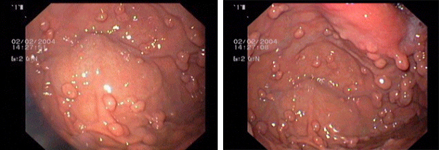

Endoscopic images:

imagen4

Fundic gland hyperplasia in the stomach, a common benign condition